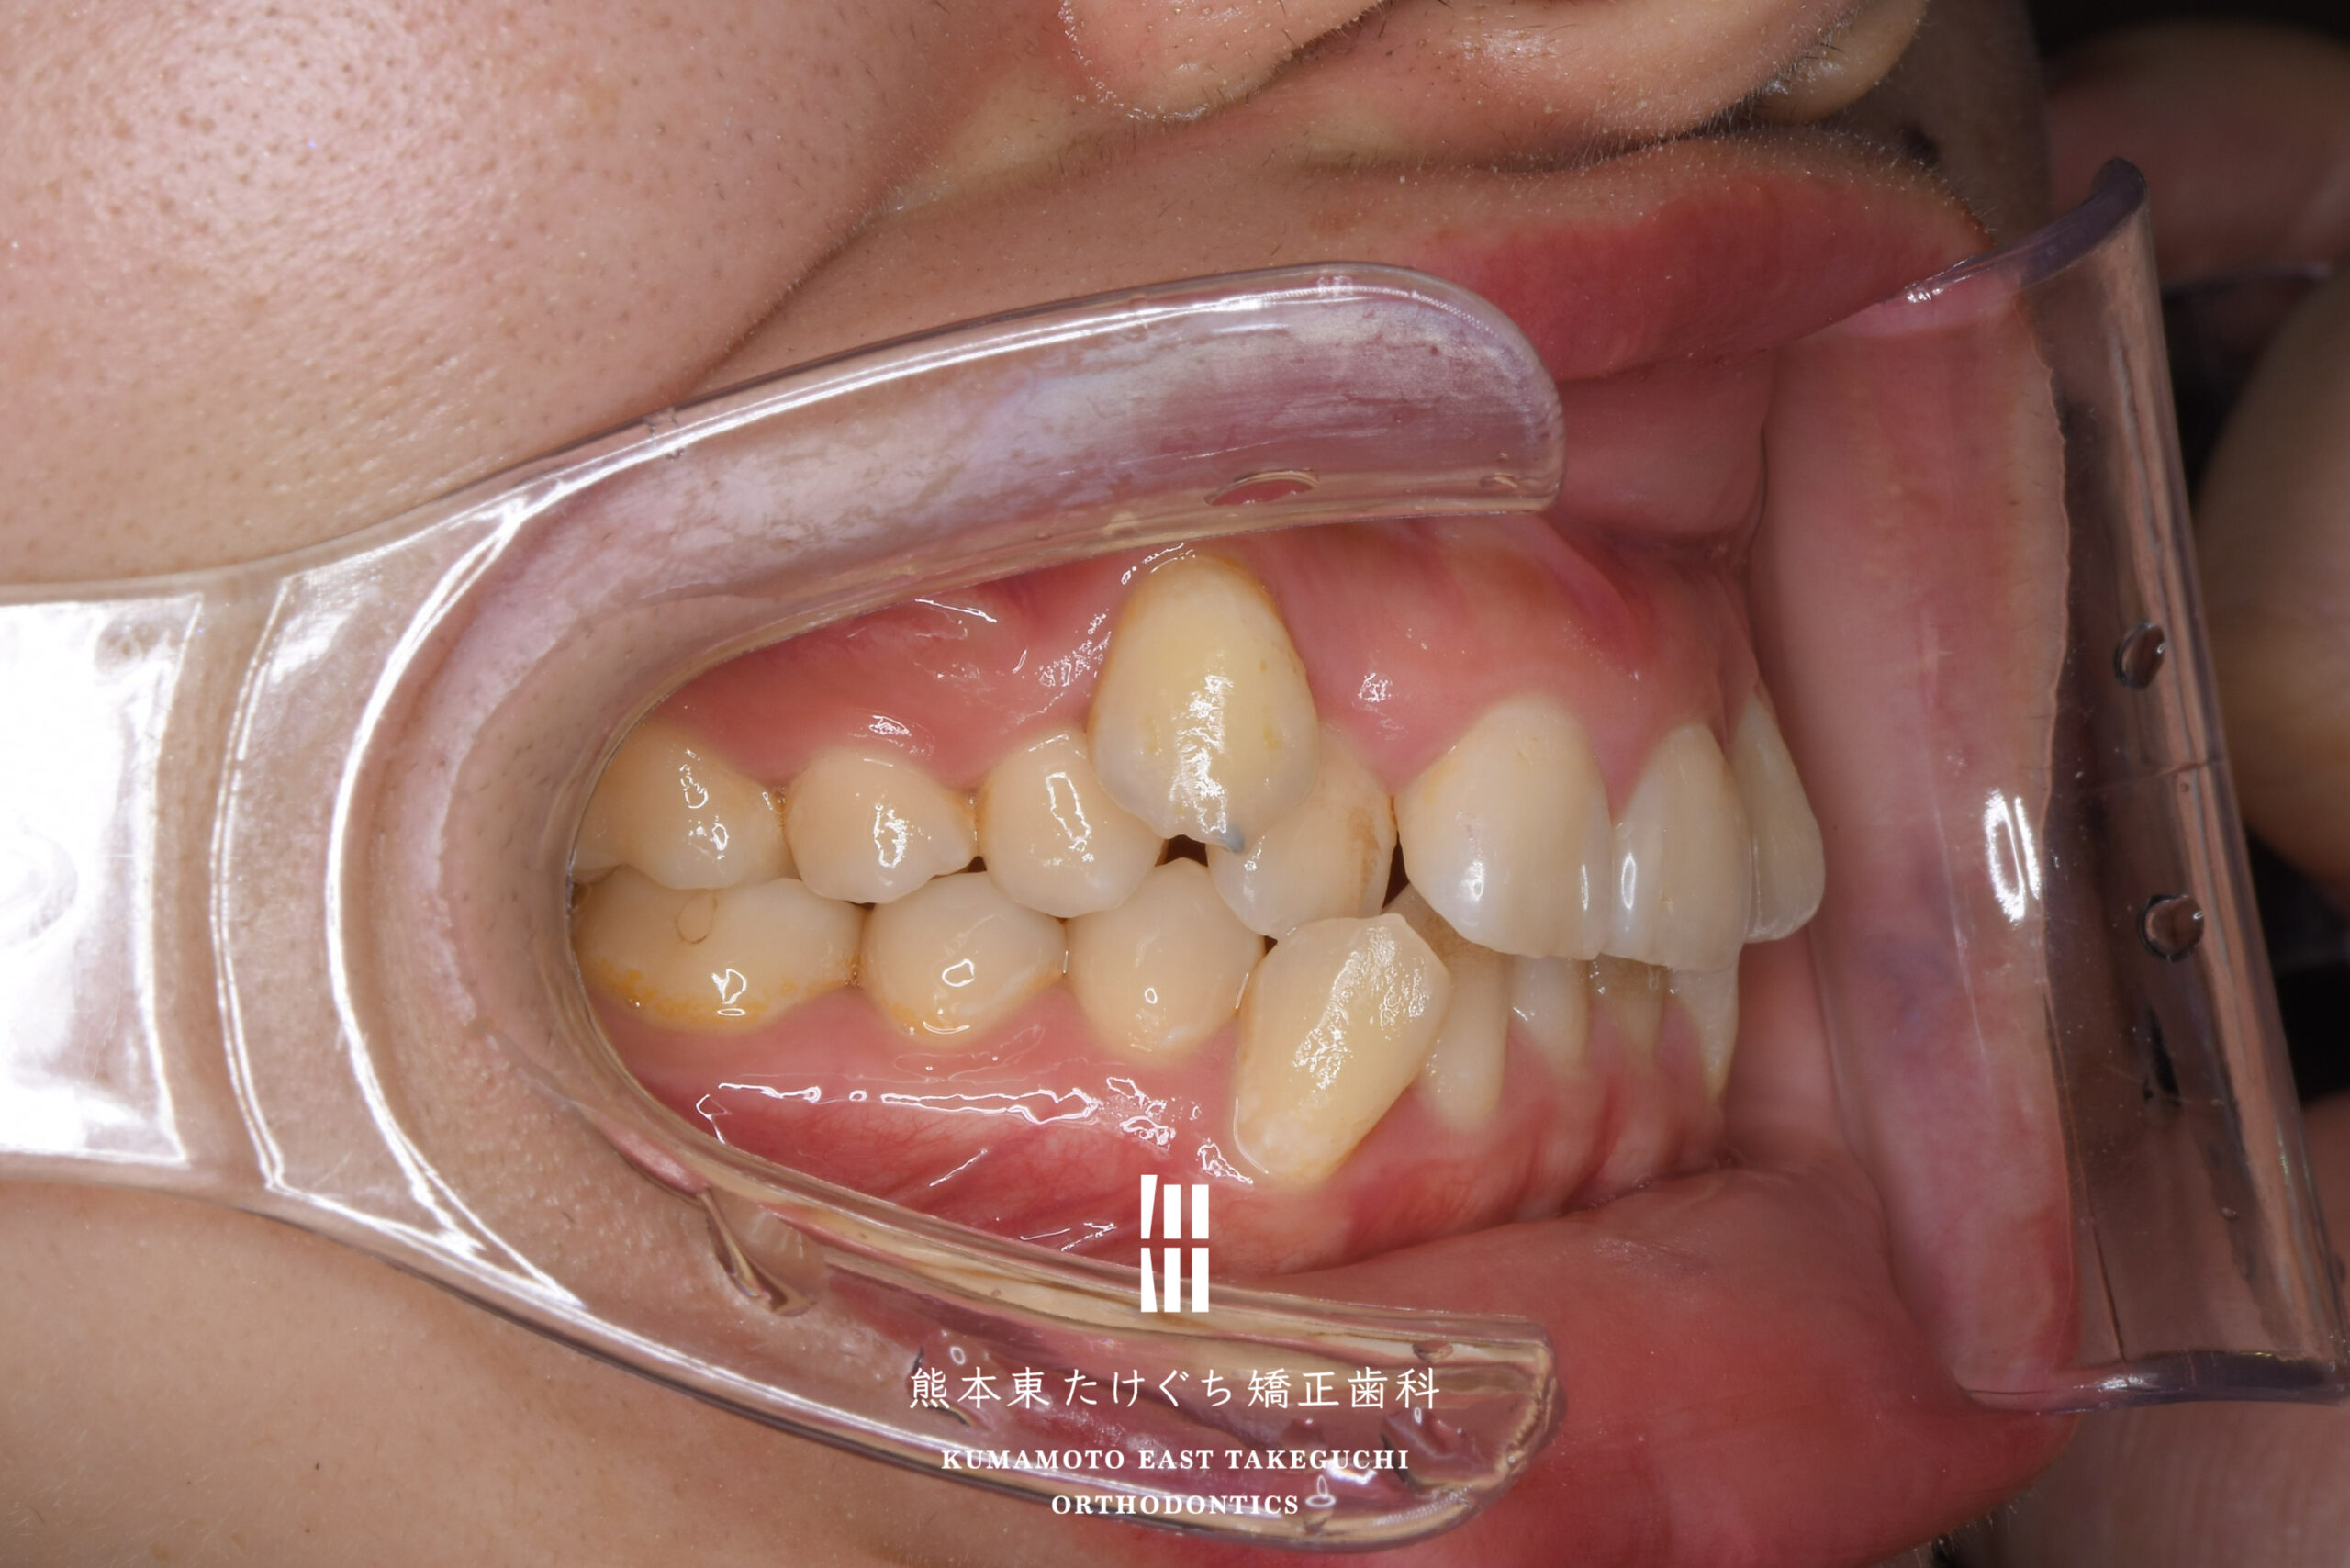

26歳女性 成人矯正 かみ合わせが深い 顎のズレ ガタガタ

主訴 ・上の歯が下の歯を覆っているため、前歯で噛みにくい

・八重歯が片方だけあるので、唇の左右差が気になる

・顔、口元のゆがみ

治療内容 正中線の偏位および過蓋吸合を伴う叢生を改善するため、上の永久歯を2本と下の永久歯1本を抜歯し、固定式ワイヤー装置を用いて治療しました。